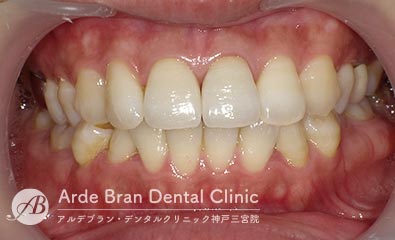

- ジルコニアセラミッククラウン(20代 女性 治療期間1カ月)

- 他院で入れた前歯の被せ物の形態や色調が隣の歯と合っていないため、やり替えたいとの事でご来院されました。切端に透明感があり、歯頚部から歯冠部にかけてグラデーションがある難しい歯でしたがトップテクニシャンとの連携により見事に再現する事が出来ました。

- 治療前

- 治療後

| 治療方法 | ジルコニアセラミッククラウンによる審美歯科治療 |

|---|---|

| 治療本数 | 2本 |

| 治療期間(通院回数) | 1カ月(4回) |

| 費用 | ジルコニアセラミッククラウン 24万円+TAX 仮歯 6千円+TAX |

| リスク副作用 | 審美歯科治療に関するリスクや副作用について、詳しくはこちらをご参照ください。 |